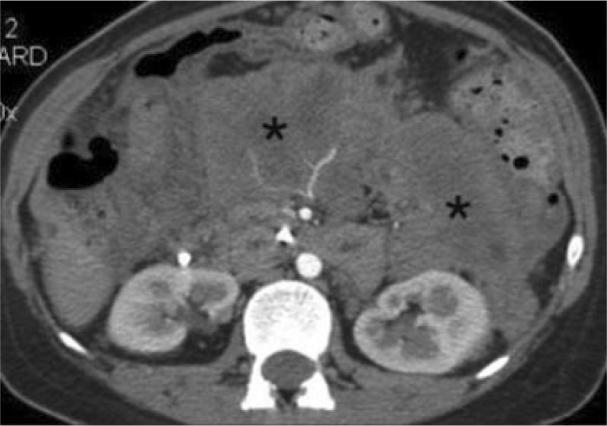

Acute pancreatitis can result in retroperitoneal fat necrosis, typically occurring in the peripancreatic region, with extension into the transverse mesocolon, omentum and mesenteric root. When evaluated with contrast enhanced computed tomography (CECT), acute peripancreatic post necrotic collections typically become lower in attenuation over time, and often appear as homogeneous fluid collections. Saponification as a complication of fat necrosis in patients with acute pancreatitis is a well recognized clinical entity. While retroperitonal fat necrosis is commonly seen on CECT, saponification is not a prominent imaging feature. We present a case of acute pancreatitis complicated by extensive saponification of fat throughout the retroperitoneum and peritoneal lining, mimicking carcinomatosis.

急性胰腺炎可导致腹膜后脂肪坏死,通常发生在胰腺周围区域,并可延伸至横结肠系膜、大网膜和肠系膜根部。当采用对比增强计算机断层扫描(CECT)评估时,急性胰腺周围坏死灶通常会随着时间推移而衰减降低,且常表现为均匀的液性病灶。作为急性胰腺炎患者脂肪坏死的并发症,皂化是一种广为人知的临床病症。虽然CECT上常见腹膜后脂肪坏死,但皂化并非显著的影像学特征。我们报告一例急性胰腺炎并发整个腹膜后和腹膜衬里广泛脂肪皂化的病例,其表现类似癌性腹膜炎。